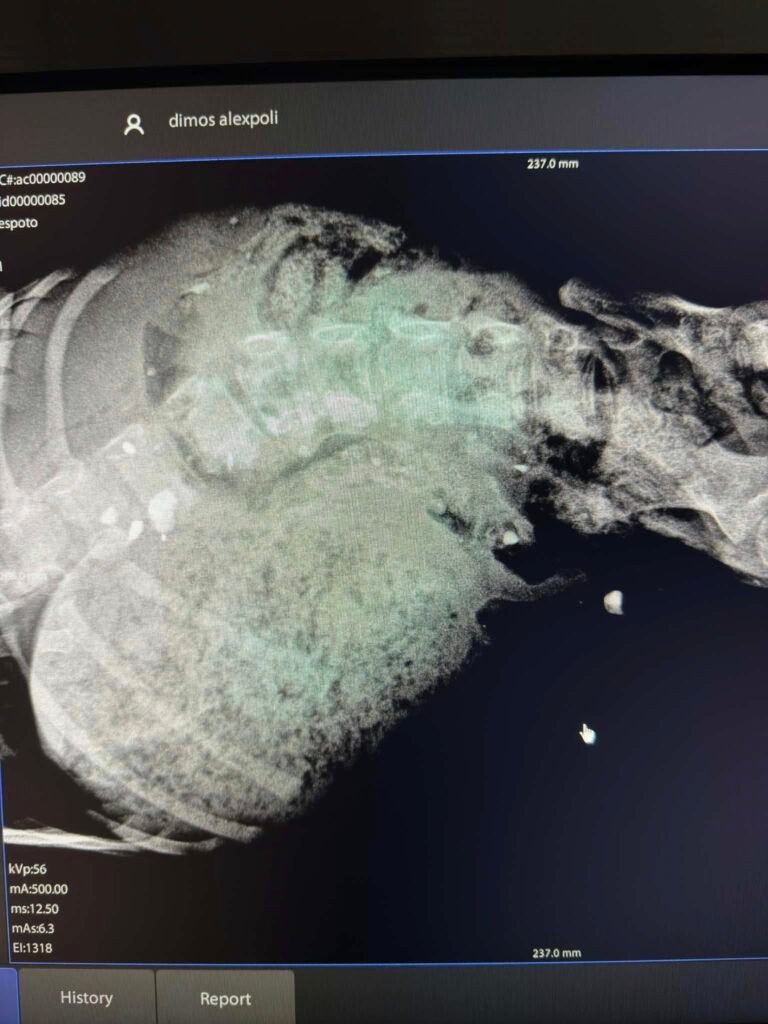

«Χτυπάει το τηλέφωνο στο κτηνιατρείο γύρω στις 12:00. Μια κοπέλα με τρεμάμενη φωνή μας λέει ότι βρήκε ενα κουτάβι μέσα στα αίματα και σέρνει τα πίσω του πόδια. Της λέμε να ενημερώσει το αρμόδιο τμήμα του Δήμου και παράλληλα ξεκινάμε για το σημείο. Ο χρόνος σε αυτές τις περιπτώσεις είναι ο εχθρός σου. Σε όλη τη διαδρομή κάνεις τις χειρότερες σκέψεις κι έχεις άγχος και αγωνία τι θα κληθείς να αντιμετωπίσεις. Φτάνουμε κοντά στο εκκλησάκι του Παΐσιου, στο ρέμα Μαΐστρου και αντικρίζουμε αυτή την μπουκίτσα. Δίπλα της η κοπέλα προσπαθεί να μείνει η ίδια ήρεμη και να κρατήσει και το κουταβάκι περιορισμένο. Γίνεται η περισυλλογή με προσοχή κι επιστρέφουμε στο κτηνιατρείο. Σε μια πρώτη κλινική εξέταση το λουκουμάκι στέκεται μεν όρθιο, αλλά δεν περπατάει. Στη νευρολογική εξέταση ευτυχώς υπαρχει ικανοποιητική ανταπόκριση και μπαίνει το ερώτημα τι συνέβη. Την σοκαριστική απάντηση θα δώσει η ακτινογραφία: πυροβολισμός με σκάγια, διάσπαρτα σε όλο το σώμα. Σοκάρεσαι τόσο που αδυνατείς να το πιστέψεις. Κοιτάζεις δίπλα σου και ρωτάς αν το βλέπουν κι αυτοί. Η θετική απάντηση που παίρνεις δεν σε λυτρώνει αλλά αντίθετα σε κάνει να νιώθεις μια απέχθεια για ένα μέρος του είδους σου που έκανε στόχο αυτό το πλασματάκι. Η Barbie, όπως την ονομάσαμε, θα παραμείνει για μερικές μέρες στο κτηνιατρείο. Θα σταθεροποιηθεί, θα σηκωθεί στα πόδια της και θα της βρούμε το καλύτερο σπιτικό. Ήδη δειλά δειλά σηκώθηκε και κούνησε την ουρά της σε μια κίνηση πρωτόγνωρη για εκείνη. Την χάιδεψε ενας άνθρωπος…

«Ήρθε στο κτηνιατρείο, αρχίσαμε την κλινική εξέταση. Φαινόταν ότι κάτι συνέβαινε στα πίσω άκρα και στη λεκάνη. Προχωρώντας, κάναμε ακτινογραφία και με τεράστια δυσάρεστη έκπληξη ανακαλύψαμε ότι το ζωάκι ήταν γεμάτο από μικρά σκάγια, προφανώς από πυροβόλο όπλο, και τώρα έγινε στόχος κάποιου διαστραμμένου για παιχνίδι, για εκτόνωση. Δεν μπορείς ποτέ να μπεις στο μυαλό ενός τέτοιου ανθρώπου, φυσικά. Κάποια σκάγια είναι σε μαλακά μόρια, σε μύες επιφανειακά. Αυτά αφαιρέθηκαν. Κάποια είναι πιο βαθιά, δεν έχουμε πρόσβαση. Δύο είναι δίπλα στο νωτιαίο μυελό και στη σπονδυλική στήλη. Δεν έχει διατομή, ευτυχώς, ο νωτιαίος μυελός.